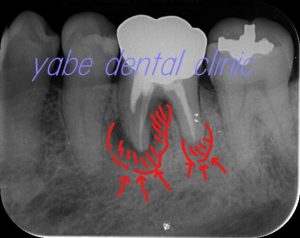

レントゲン写真を見てみましょう。

症状が出ている歯牙はすでに根管充填がなされていて、近心根と遠心根には歯根を取り囲むように透過像が認められます。

さらによく見てみると近心根では根分岐部にまで透過像が及んでいます。

「もしかするとパーフォーレーションしているのかな?。」

それが、最初にレントゲンを見た感想です。後日、歯科用CBCTを撮影してみるとやはり近心根の根分岐部あたりにパーフォレーションを疑わせる透過像が認められました。